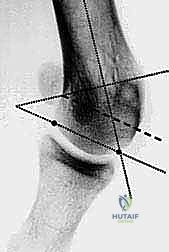

- التصوير بالأشعة السينية الدقيقة (Weight-Bearing X-Rays): وهي خطوة حاسمة. يجب أن تؤخذ الأشعة والمريض واقف (يحمل وزنه على قدمه) لإظهار الحجم الحقيقي للتشوه.

- القياسات الهندسية لزوايا القدم: يقوم الدكتور هطيف بقياس زوايا محددة لتحديد نوع الجراحة، أهمها:

- HVA (Hallux Valgus Angle): زاوية انحراف الإبهام (الطبيعي أقل من 15 درجة).

- IMA (Intermetatarsal Angle): الزاوية بين العظمة المشطية الأولى والثانية (الطبيعي أقل من 9 درجات).

- DMAA (Distal Metatarsal Articular Angle): زاوية سطح المفصل، وهي الزاوية الأهم التي تحدد الحاجة لتقنية "ش